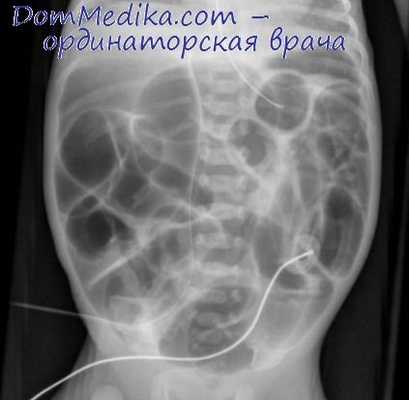

Различия между этими видами кишечной непроходимости лучше выявляются при обычном рентгенологическом исследовании брюшной полости. Существуют два пути ведения таких пациентов: консервативное и оперативное лечение после соответствующей подготовки.

Но при полной кишечной непроходимости (на рентгенограмме отсутствует газ в толстой кишке выше проекции прямой кишки) шансы на спонтанное ее разрешение невелики, и ряд хирургов сразу склоняются в пользу оперативного лечения. При раздражении брюшины, лихорадке, прогрессировании лейкоцитоза показания к лапаротомии являются абсолютными.

Рентгенография ОБП при кишечной непроходимости